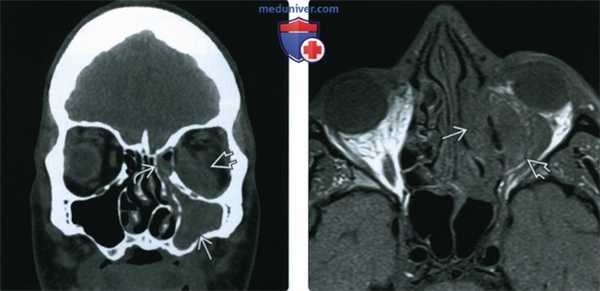

(Слева) При аксиальной КТ без КУ у пациента с диабетом и мукормикозом (ОИГРС) определяется циркулярное поражение правой верхнечелюстной пазухи с выраженными эрозиями задней стенки и замещением жировой клетчатки ретроантральной области и крылонебной ямки мягкотканным компонентом.

(Справа) При аксиальной МРТ Т1 С+ FS визуализируются фокальные неконтрастирующи-еся зоны в слизистой оболочке верхнечелюстной пазухи, соотносящиеся с некротическим струпом, жировая клетчатка ретро-антральной области и крылонебной ямки замещена мягкотканный компонентом.

(Слева) При корональной КТ без КУ у пациента с диабетом, почечной недостаточностью, жалобами на боль в глазу определяется снижение пневматизации левой верхнечелюстной пазухи, ячеек решетчатой кости с выраженным эктра- и интракональным ретроорбитальным мягкотканным компонентом, окружающим и смещающим внутреннюю и нижнюю прямые мышцы.

(Справа) При аксиальной МРТ Т1 определяется поражение решетчатой пазухи с чрескостным распространением в ретрорбитальные мягкие ткани. Была выполнена экзентерация орбиты, максиллэктомия, этмоидэктомия, подтвердился ОИГРС (Mucor).